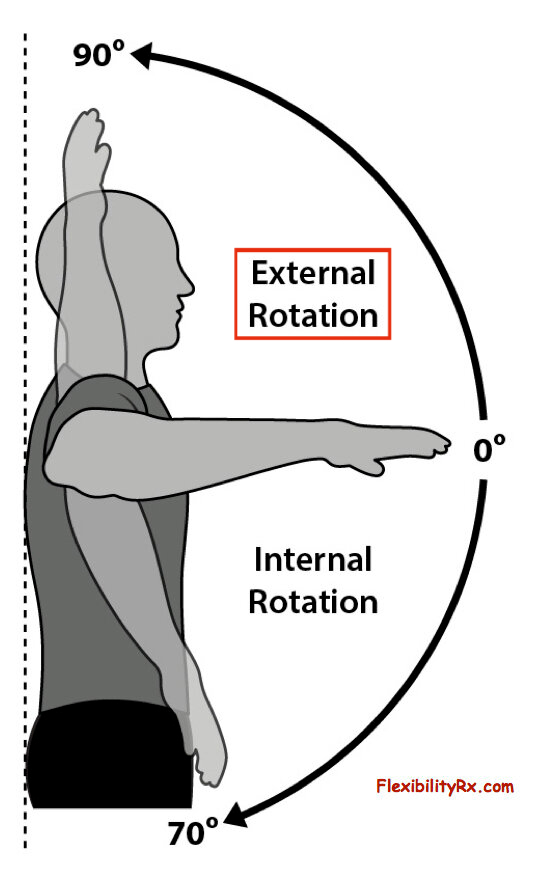

ㆍ회전외회전(ER) / 내회전(IR)

참고로 어깨 앞쪽 전방탈구는 외전, 신전, 외회전 시 발생되며 위와같이 관절와의 기능적인 앞쪽 기울어짐상태 시 더 잘 발생할 수 있습니다.

반면 어깨 뒤쪽은 상대적으로 관절와와 상완골두가 좁아지며 외회전, 수평외전 시 극상근, 극하근이 관절와순과 충돌이 많아지며 내적충돌을 일으킬 수 있습니다.(Internal impingement) 이 때 내적충돌은 전상방, 후상방에서 각각 일어날 수 있고, 주로 후상방에서 나타납니다.

3. 외회전(ER)의 회복